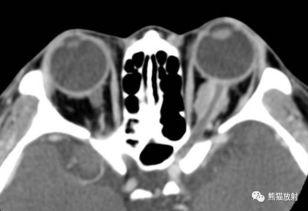

诊断是战斗的第一步。医生会通过影像学检查、血液检查、病理学检查等多种手段来确定肿瘤的类型、大小、位置等信息。治疗则包括手术、放疗、化疗、靶向治疗、免疫治疗等多种手段。